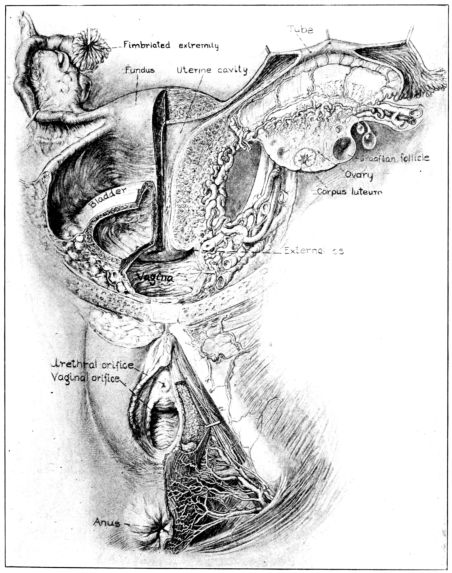

| 12. | Sagittal section of female generative tract | 35 |

The female organs of reproduction are divided into two groups, the internal and the external genitals. With them are usually considered certain other structures: the ureters, bladder, urethra, rectum and the perineum, because of their close proximity (Fig. 10.); and the breasts, because of their functional relation to the reproductive organs.

Internal Genitalia. The internal organs of generation are contained in the true pelvic cavity and comprise the uterus and vagina in the centre, an ovary and Fallopian tube on each side, together with their various ligaments, membranes, nerves and blood vessels and a certain amount of fat and connective tissue.

Fig. 10.—Anterior view of female generative tract, showing both external and internal organs. Drawn by Max Brodel. (Used by permission of A. J. Nystrom & Co., Chicago.)

Fig. 12.—Sagittal section of female generative tract. Drawn by Max Brodel. (Used by permission of A. J. Nystrom & Co., Chicago.)